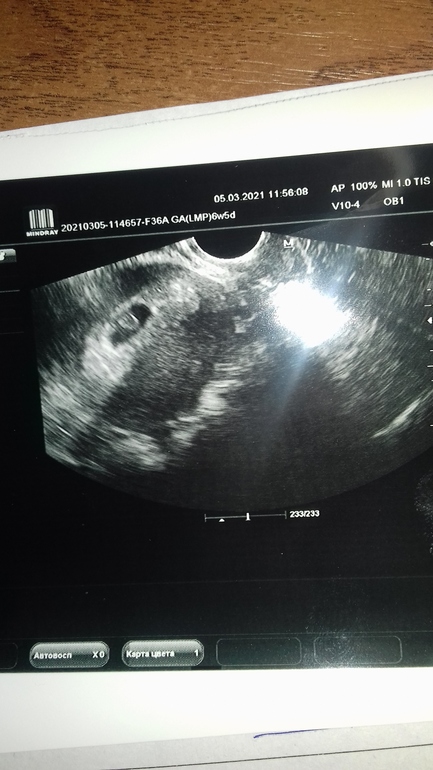

Сегодня, как многие знают, ездила на УЗИ, так как были выделения кровяные...

И заодно нас вновь сфоткали))) Блин так подрос бублик мой за 3 дня☺️

соответствуем своим 6,5 неделям)))

у меня угроза была... и когда увидела, что сердечко бьется.. груз снят был